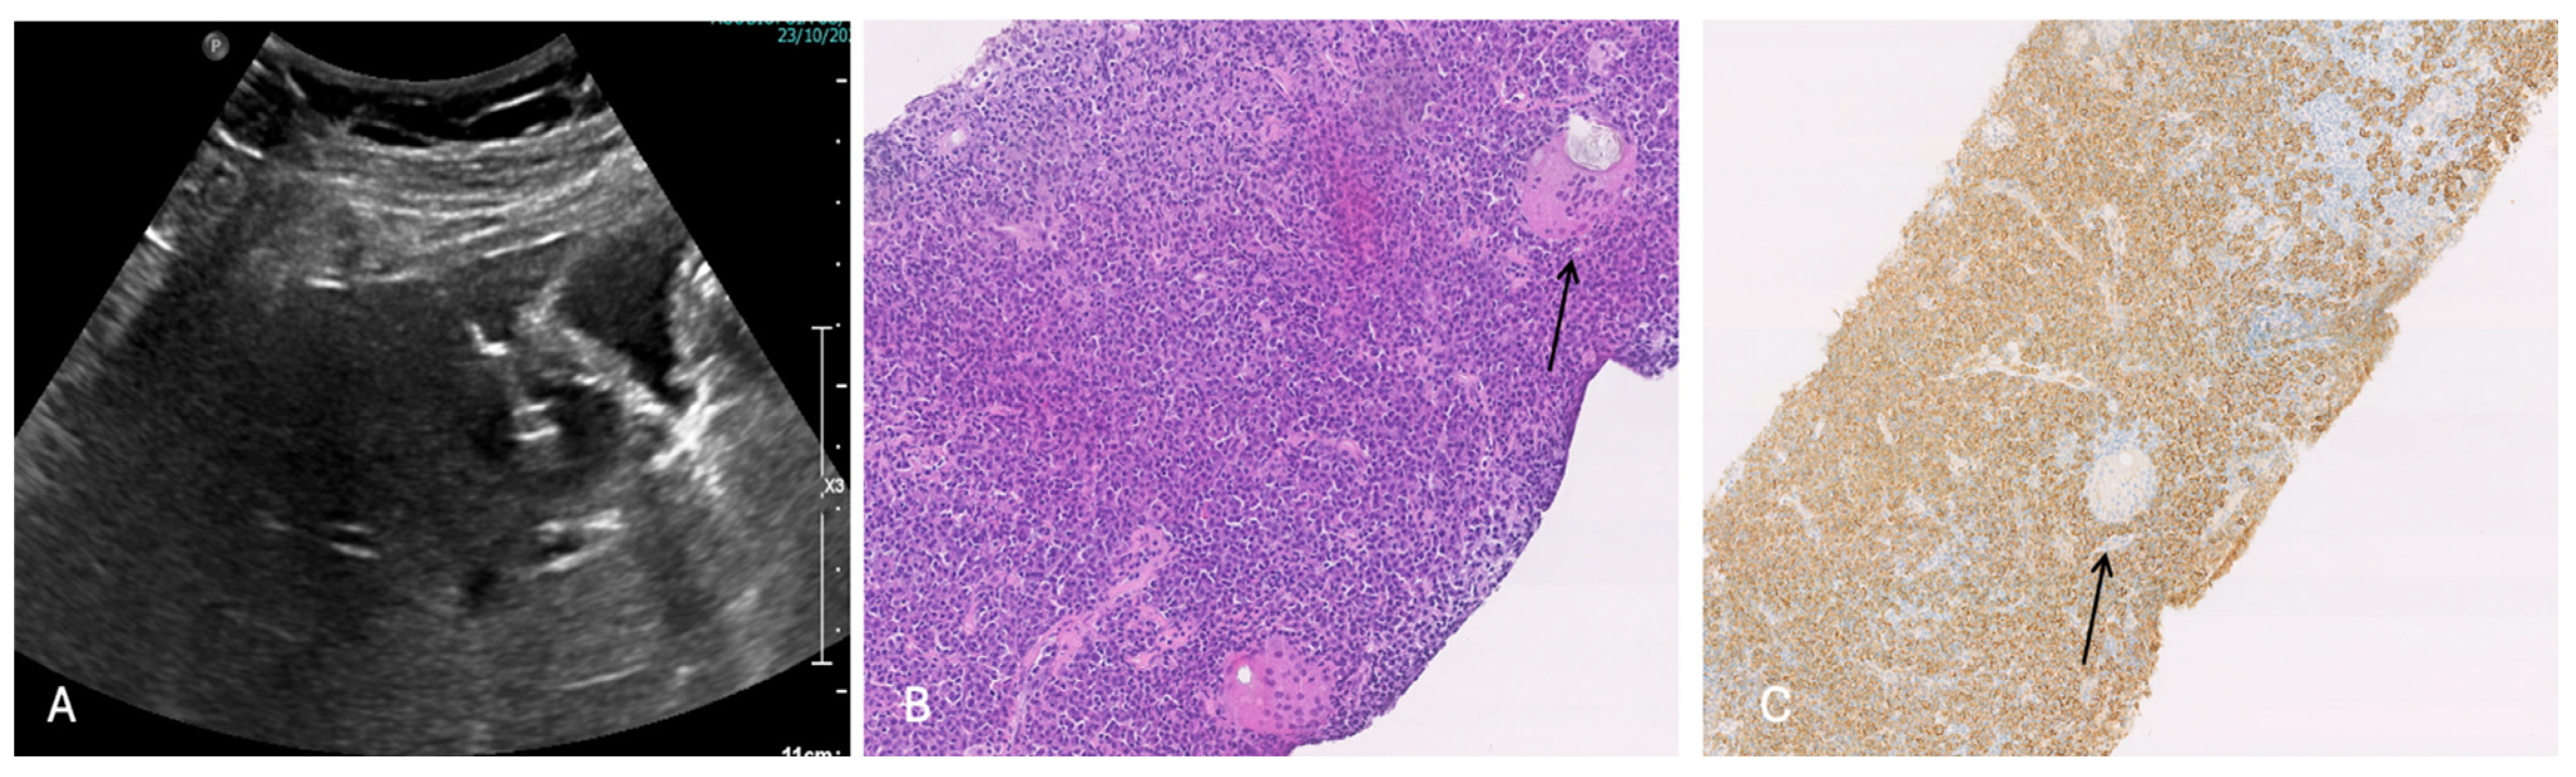

3.2.1. Case 1

3.2.2. Case 2